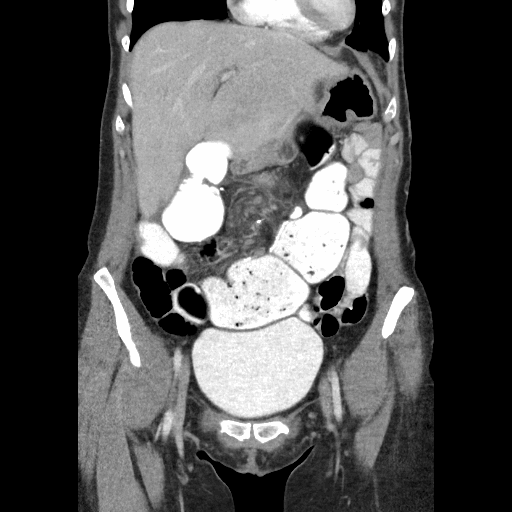

Pouchography, CT, and MRI Features of Ileal J PouchAnal Anastomosis AJR Ileal Pouchoscopy ileoanal anastomosis surgery removes the large intestine and makes a pouch inside the body that allows a person. Find a specialist and schedule an appointment today. cleveland clinic's ileal pouch and j pouch surgery center is a top ranked program in nation. pouchitis and ileal pouch disorders are common in patients with restorative proctocolectomy and ileal. . Ileal Pouchoscopy.